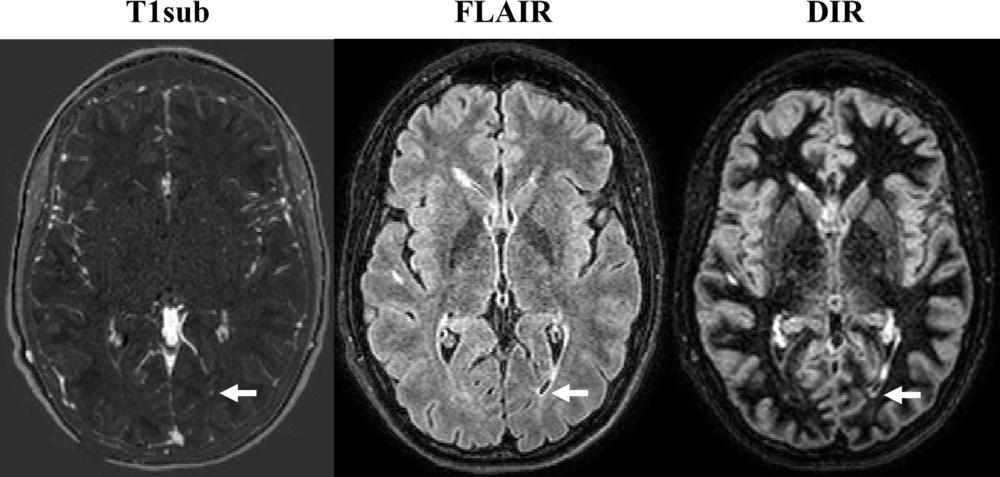

Dr. Wiestler credited an image subtraction pipeline developed and researched at his facility for the powerful sensitivity of the non-contrast MRI in detecting newly occurring lesions. The approach combines 3-D MRI and subtraction techniques, which cancel out unchanged areas in the follow-up image, substantially improving visualization of new or enlarging white matter lesions.

This combination of 3-D sequences and subtraction techniques is key to improving sensitivity for detecting newly occurred lesions, Dr. Wiestler said.